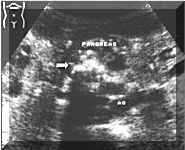

Picture1.

Multiple

pancreatic

calcifications

(see

arrow).